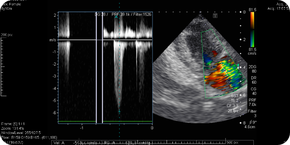

心臓の聴診時に心雑音が聞こえます。もし心雑音があった場合、レントゲン検査やエコー検査をおすすめすることがあります。これらの検査で重症度や、治療方針が決定されます。心臓の聴診で簡単に発見することができる病気なので、ワクチン接種や日常的な健康診断でも容易に発見できます。

多くの場合、利尿薬、血行を調整するお薬、強心薬などの内服薬で治療します。レントゲンや心エコー検査で逆流の程度や心拡大の程度を把握しながら、内服薬の種類や量を細かく調整します。これらの治療でうっ血性心不全の症状を緩和します。

レントゲンやエコー検査はうっ血性心不全の重症度、治療方針を決定するうえで欠かせない検査です。